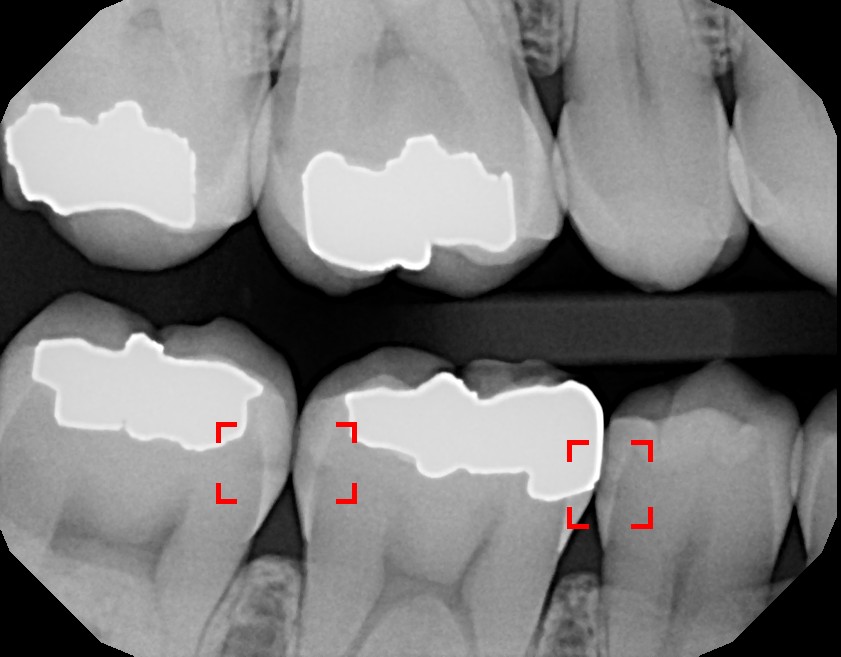

How Much Radiation Is in a Dental X-Ray?

To put things in perspective, an average resident of the U.S. receives over 360 mrem every year from background sources. This comes from all over the place: outer space, radioactive materials in the earth, small amounts of radioactive material in foods and products that we use, even over people. Variances in lifestyle likewise cause variances in each individual's total exposure. For example: an individual who flies often is exposed to more background radiation than someone who does not.

While steps should be taken to limit x-ray radiation exposure, dental x-rays are very low dose and are crucial for proper diagnosis. Without them, much of the oral cavity cannot be viewed.